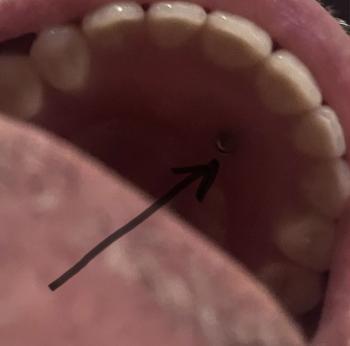

This CBCT image shows a posterior mandibular area with a natural molar next to an existing dental implant. The natural tooth presents a clear apical radiolucency, indicating infection at the root apex. Bone density changes are visible between the infected tooth and the implant site.

Periapical radiolucency suggests chronic apical periodontitis

Infection is in close proximity to implant threads

Chronic apical infection of natural tooth

Secondary risk of peri-implant bone involvement